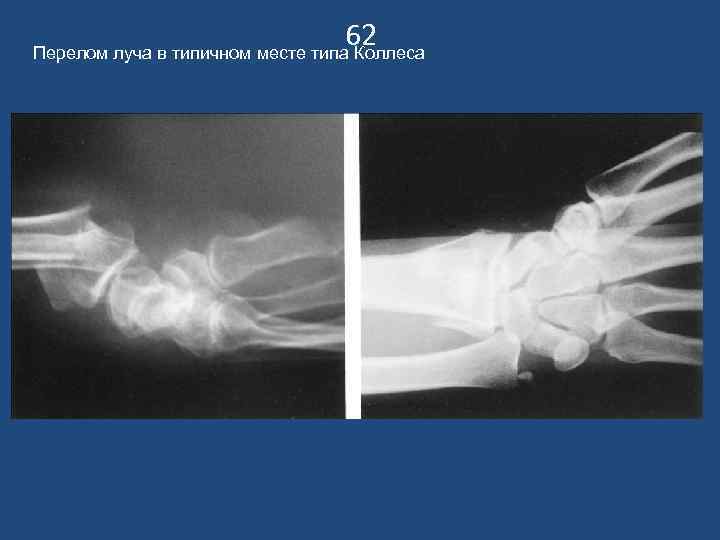

62 Перелом луча в типичном месте типа Коллеса